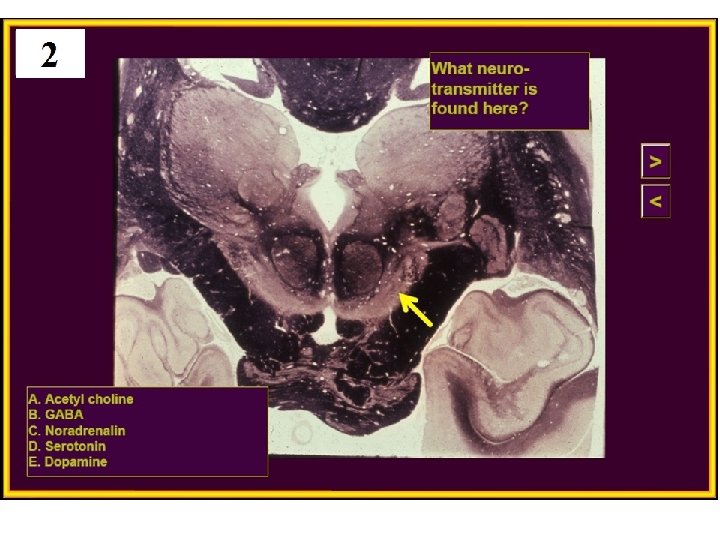

20. Huntington’s disease is caused by degeneration of which nucleus? A) Subthalamic B) Globus pallidus C) Substantia nigra D) Caudate E) VPL